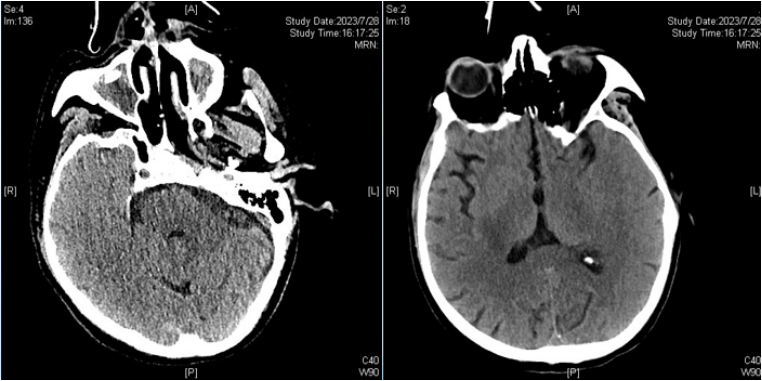

影像学(8月14日)

胸部CT:双肺感染较前吸收好转,双侧胸腔积液较前减少。

头颅CT:右侧大脑半球低密度影范围较前增大,考虑脑梗死并右侧颞叶出血可能,上颌窦炎,真菌感染可能(图8)

图片

图8  患者头颅CT(2023-08-14)